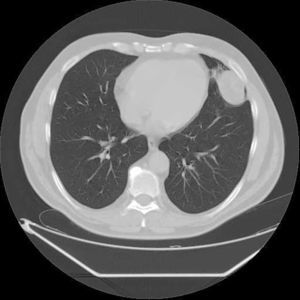

Un paciente varón de 58 años de edad se presentó con dolor en el hemitórax izquierdo que se irradiaba al brazo izquierdo y el hombro. La radiografía de tórax reveló una lesión no definida en el lóbulo superior del pulmón izquierdo. Una tomografía computarizada multicorte mostró un nódulo pulmonar intraparenquimatoso redondeado y localizado periféricamente que medía 53×54mm y se situaba en la parte inferior del lóbulo superior del pulmón izquierdo (língula). La lesión estaba en contacto con el diafragma, el pericardio y la pleura parietal (fig. 1).

En nuestro caso, el estudio de tomografía computarizada multicorte y la inspección intraoperatoria del pulmón mostraron la lesión pulmonar intraparenquimatosa en contacto con el diafragma, el pericardio y la pleura parietal, y simulaba clínicamente una neoplasia maligna. Por lo tanto, la lobectomía se consideró el tratamiento de elección. Aunque son raros, se deben tener en cuenta los lipomas pulmonares intraparenquimatosos en el diagnóstico diferencial de los nódulos pulmonares localizados periféricamente para que se pueda planificar y modificar cuidadosamente el procedimiento quirúrgico.